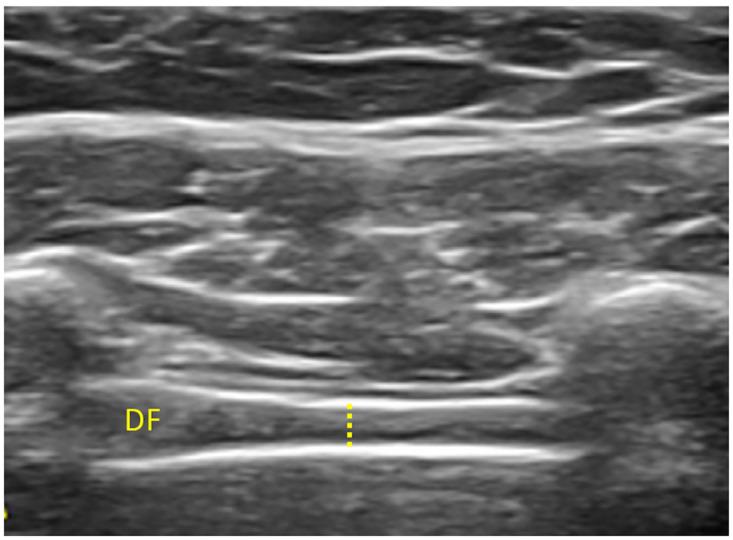

A cross-sectional observational pilot study was performed. A total sample of 24 participants were recruited from a private medical center (Madrid, Spain): Covid-19 (n = 12) and healthy controls (n = 12). The external oblique (EO), internal oblique (IO), transversus abdominis (TrA), rectus abdominis (RA), interrecti distance (IRD) and diaphragm thickness were assessed using USI during inspiration, expiration and during contraction.

USI measurements of the thickness of EO, IO, TrA, RA, IRD and the diaphragm did not differ significantly between groups during inspiration, expiration or during contraction (all P > 0.05).

These preliminary results suggest that the morphology of the abdominal muscles and diaphragm is not altered in people with a recent history of moderate Covid-19 infection.